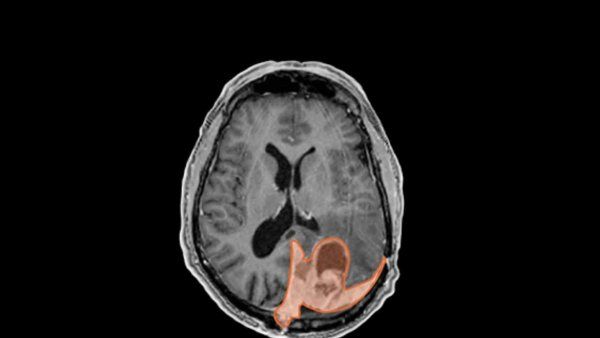

Could This Birth Control Shot Increase Your Risk for Brain Tumor?

UCSF radiation oncologist David Raleigh, MD, PhD, studies the link between brain tumors and injectable birth control.